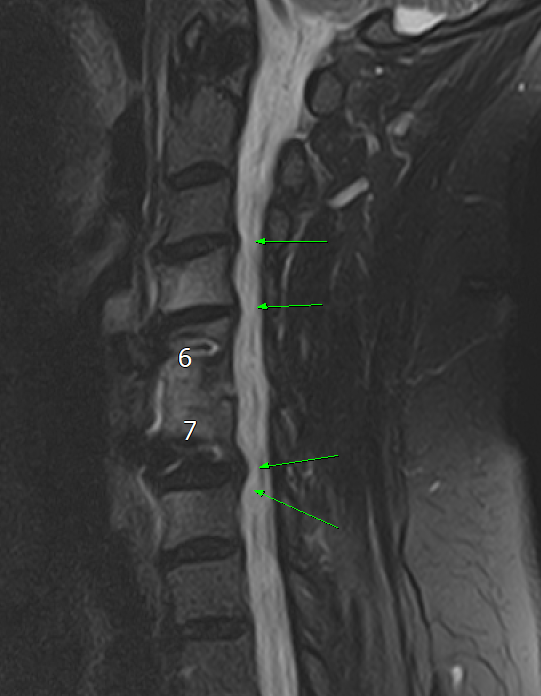

경추 6-7번 사이에 유합술이 되어있다.

그러나, 유합술이 되어있는 상태에서는 해당 유합술 인접부에 문제가 생기는 경우가 흔하다.

Adjacent segement disease (인접분절 질환) 이라고

불리는 것인데,

척추 유합술을 하고 난 이후

원래는 골고루 분산되던 힘이 유합술로 인해 분산이 이루어지지 않으며

위, 아래 쪽의 척추 및 디스크, 신경이 나오는 길 쪽으로 퇴행성 변화 등을 일으키는 것이다.

이로 인해 협착증이나 디스크 증상이 나타날 수 있다.

MRI 검사가 필요하다.

결국 환자분이 느끼는 증상은 목에서 올 가능성이 높고,

X-ray 로는 제한적인 정보밖에 알 수 없기 때문에 MRI 를 찍어야 한다.

예상대로, 6-7번 유합술 된 주변,

C4-5, C5-6, C7-C8 사이로

디스크 탈출 및 퇴행성 변화, 협착 등

인접분절 질환을 보여주는 양상을 확인할 수 있다.